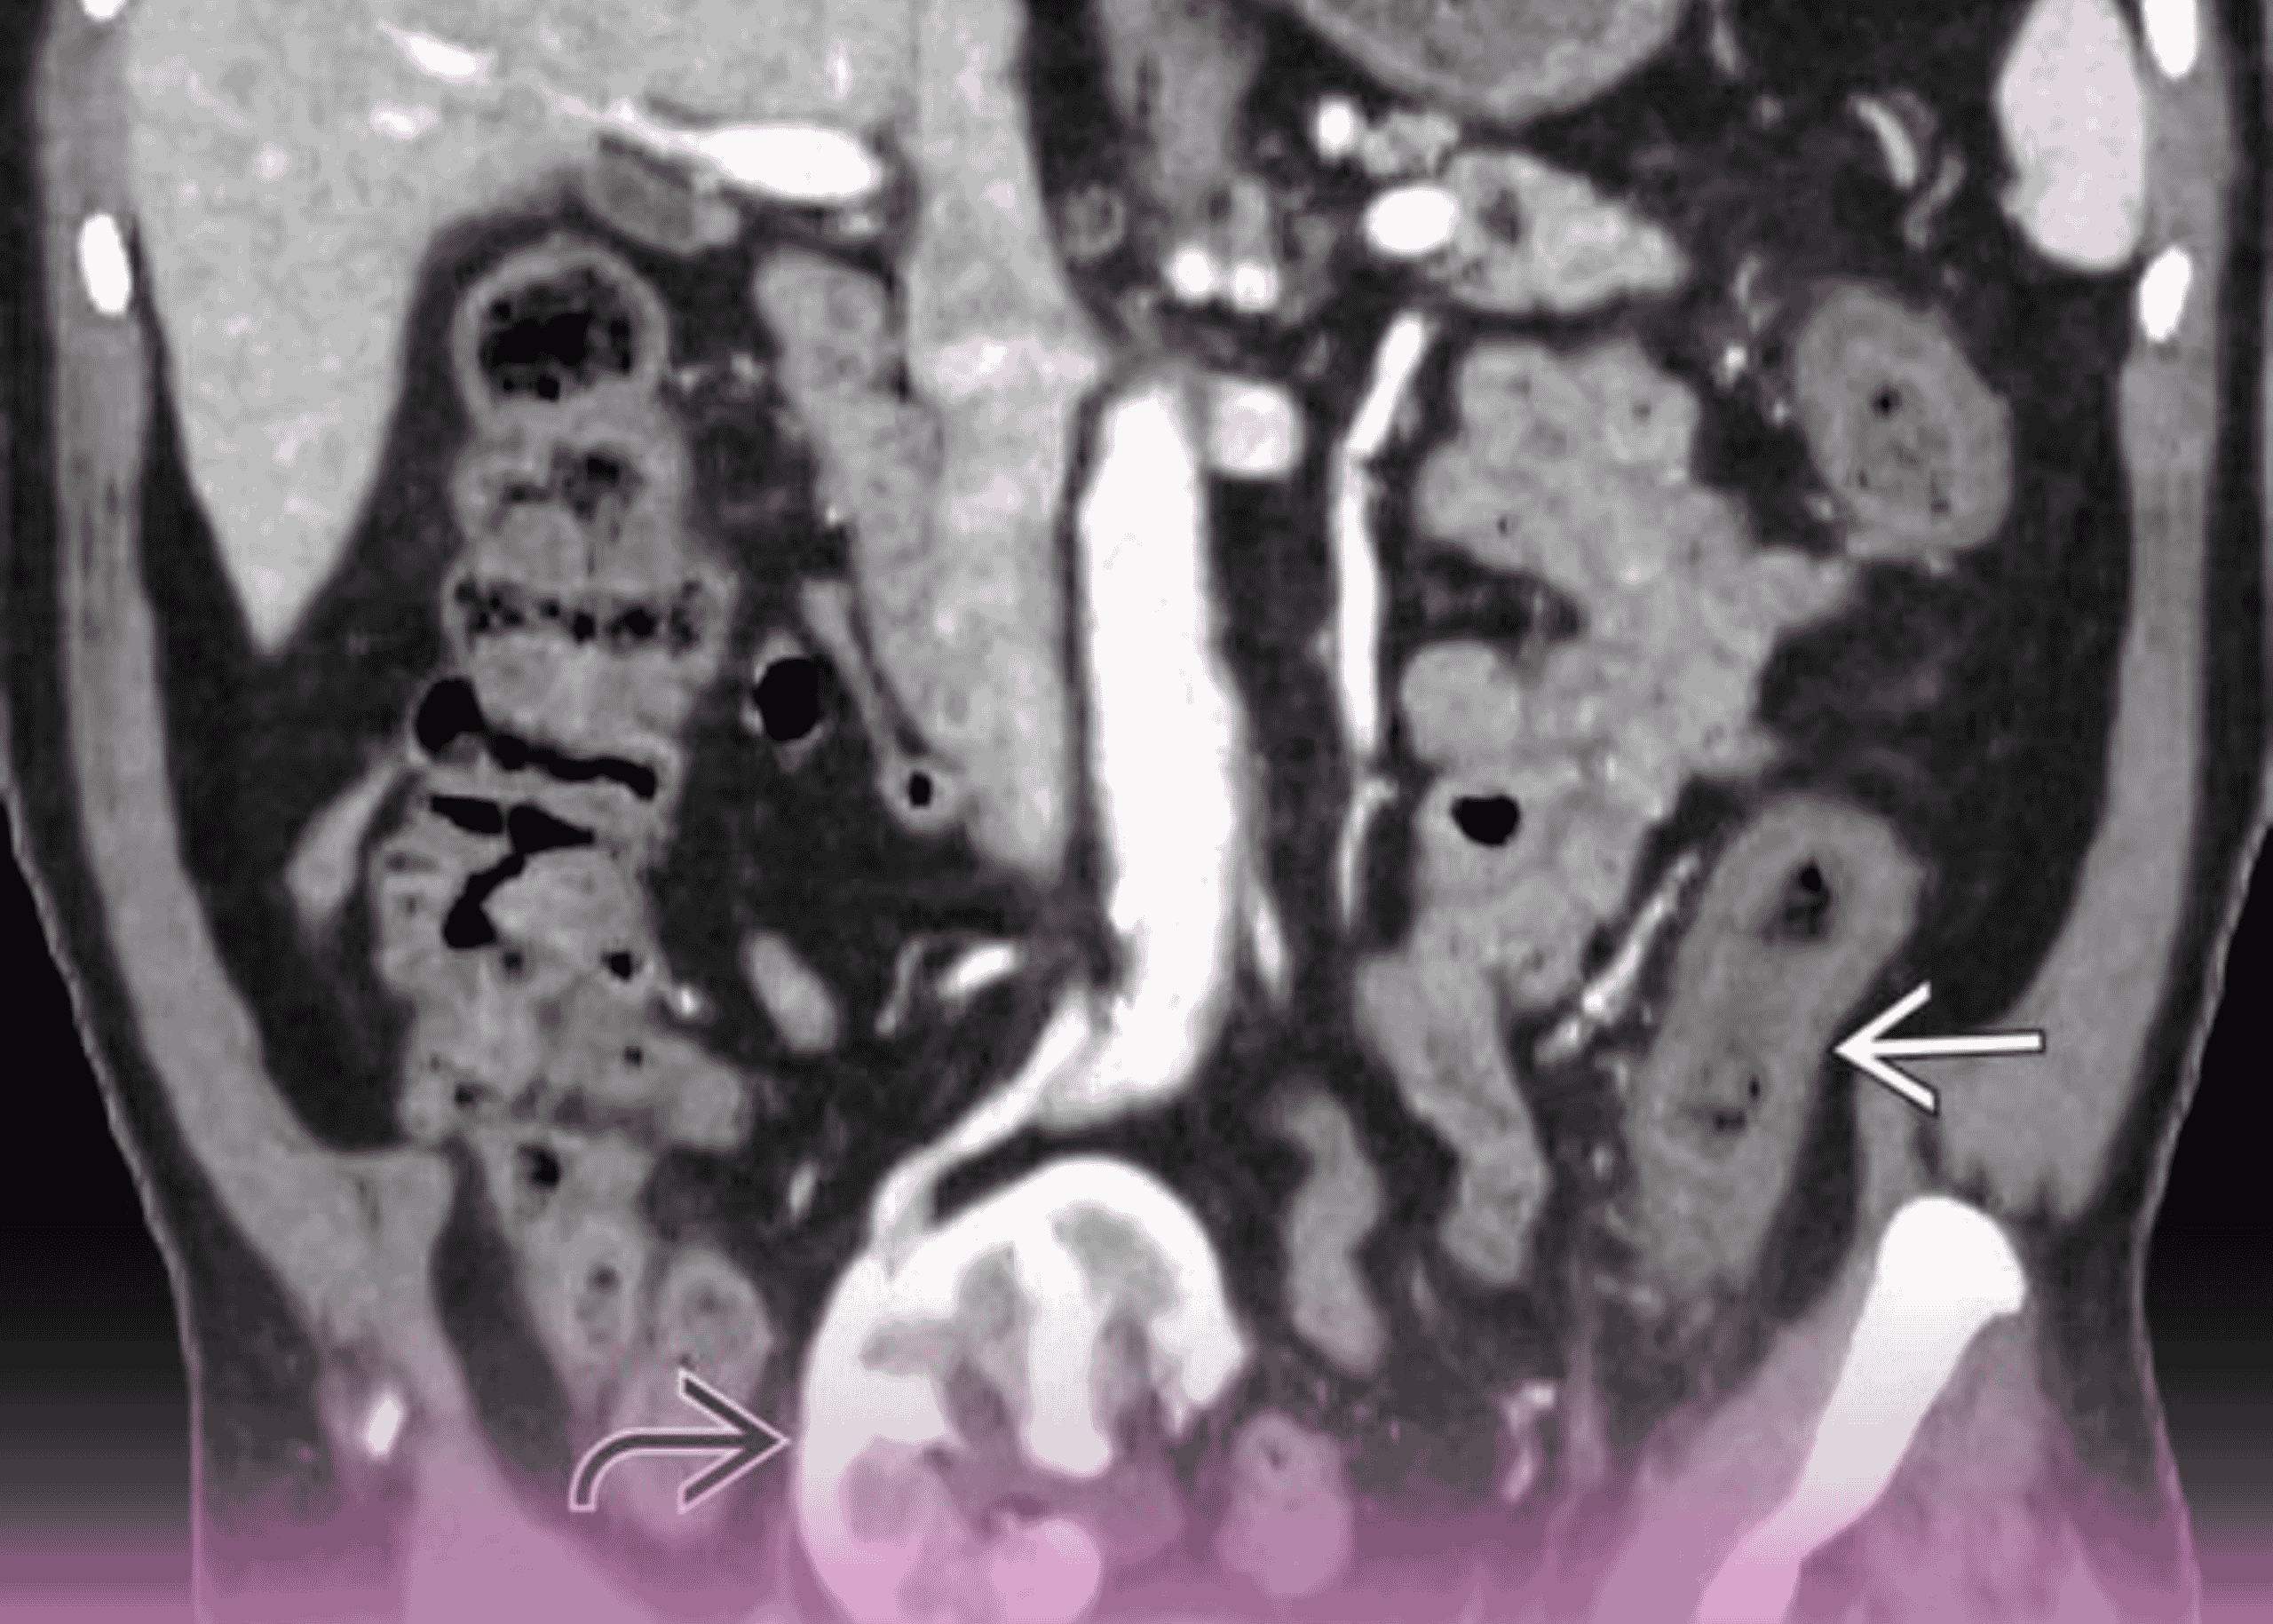

التهاب القولون الإقفاري مع ثقوب متعددة: التدبير الجراحي لحالة مهددة للحياة

مقدمة التهاب القولون الإقفاري يمثل تحدياً كبيراً في جراحة الجهاز الهضمي، خاصة